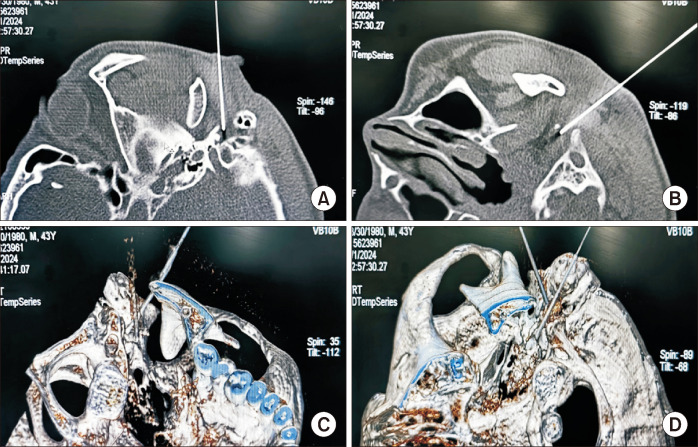

CT-guided extracranial radiofrequency of multiple groups of cranial nerves for the treatment of compound Meige's syndrome.

{"title":"CT-guided extracranial radiofrequency of multiple groups of cranial nerves for the treatment of compound Meige's syndrome.","authors":"Huiling Peng, Chunxiao Wang, Binyue Xin, Bing Huang","doi":"10.3344/kjp.24415","DOIUrl":null,"url":null,"abstract":"","PeriodicalId":56252,"journal":{"name":"Korean Journal of Pain","volume":"38 2","pages":"209-212"},"PeriodicalIF":3.1000,"publicationDate":"2025-04-01","publicationTypes":"Journal Article","fieldsOfStudy":null,"isOpenAccess":false,"openAccessPdf":"https://www.ncbi.nlm.nih.gov/pmc/articles/PMC11965996/pdf/","citationCount":"0","resultStr":null,"platform":"Semanticscholar","paperid":null,"PeriodicalName":"Korean Journal of Pain","FirstCategoryId":"3","ListUrlMain":"https://doi.org/10.3344/kjp.24415","RegionNum":3,"RegionCategory":"医学","ArticlePicture":[],"TitleCN":null,"AbstractTextCN":null,"PMCID":null,"EPubDate":"","PubModel":"","JCR":"Q2","JCRName":"CLINICAL NEUROLOGY","Score":null,"Total":0}